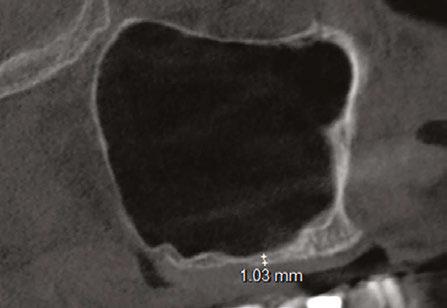

Let’s review a recent case that showcases the rationale and techniques of the top three. It is common to utilize several suturing techniques in surgical closure, especially in larger grafting cases. In the following case, a lateral sinus lift was performed, and all three techniques were used to their full effect. Simple interrupted sutures are used to close small incisions and place tissue margins accurately back in place; horizontal mattress sutures are used to hold membranes in place and relieve tension over the incision line, and running interlocking continuous sutures are used to close longer incisions with watertight closure for maximum healing potential via primary closure.

A patient presented with a failing bridge on the upper left that is supported by three mini implants. The implants directly perforate the sinus and only ~2mm of residual bone height remains on the crest (Figure 8). The mini implants were removed, and a

Figures 7A and 7B: Horizontal mattress sutures are useful for helping to secure membranes in grafting situations and relieving tension in longer span incisions Figures 8A and 8B: The pre-op condition of the patient with mini implants engaging minimal bone and perforating the sinus. The patient’s implant supported bridge was loose and causing discomfort Figure 9: A periosteal biting mattress engages only the periosteum in the buccal vestibule and exit and re-enters on the lingual tissue, helping to secure the membrane tightly over the window and crest